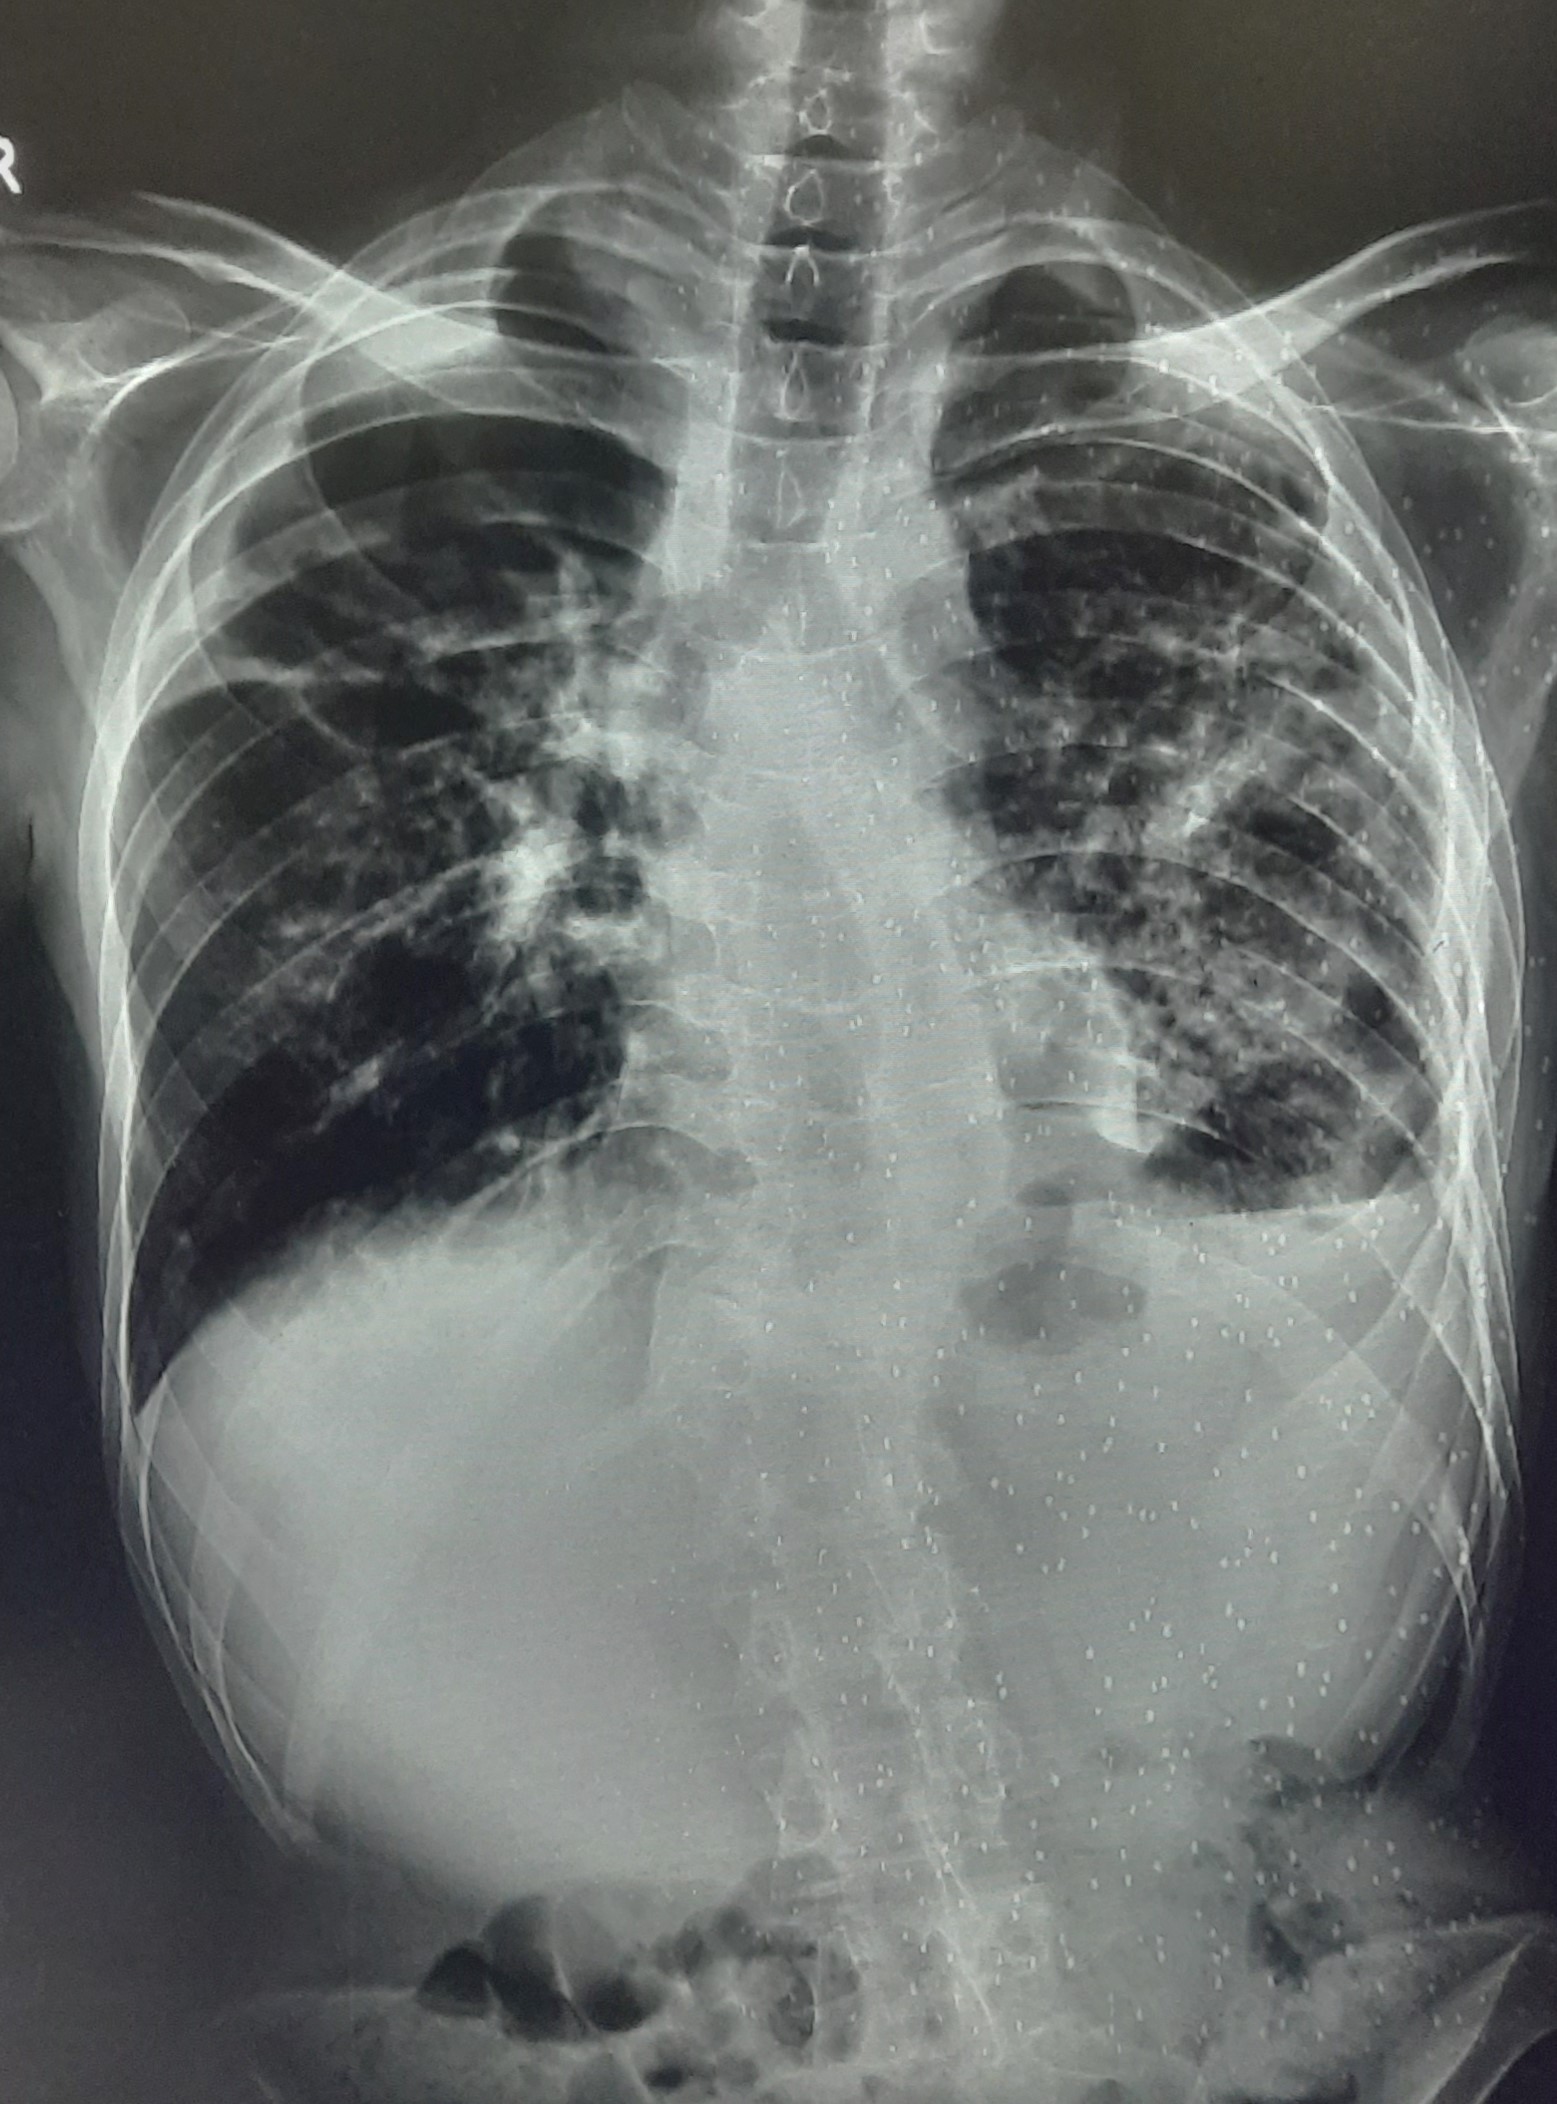

| 209 | IGGMC, Nagpur, Nagpur | P2 | 29-4263 | MONIKA KAITHAL | Consent taken on Paper | 47 Yrs. |

Provisional Diag : B/L LUNG CONSOLIDATION PNEUMONIA?

Final Diag : B/L CONSOLIDATION/PNEUMONIA |

TB Case (Confirmed) | B/L LUNG CONSOLIDATION | Abnormality visible on x-ray |

View |